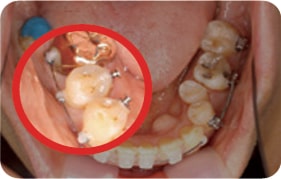

Case 2

2017. 08. 07

2018. 04. 16